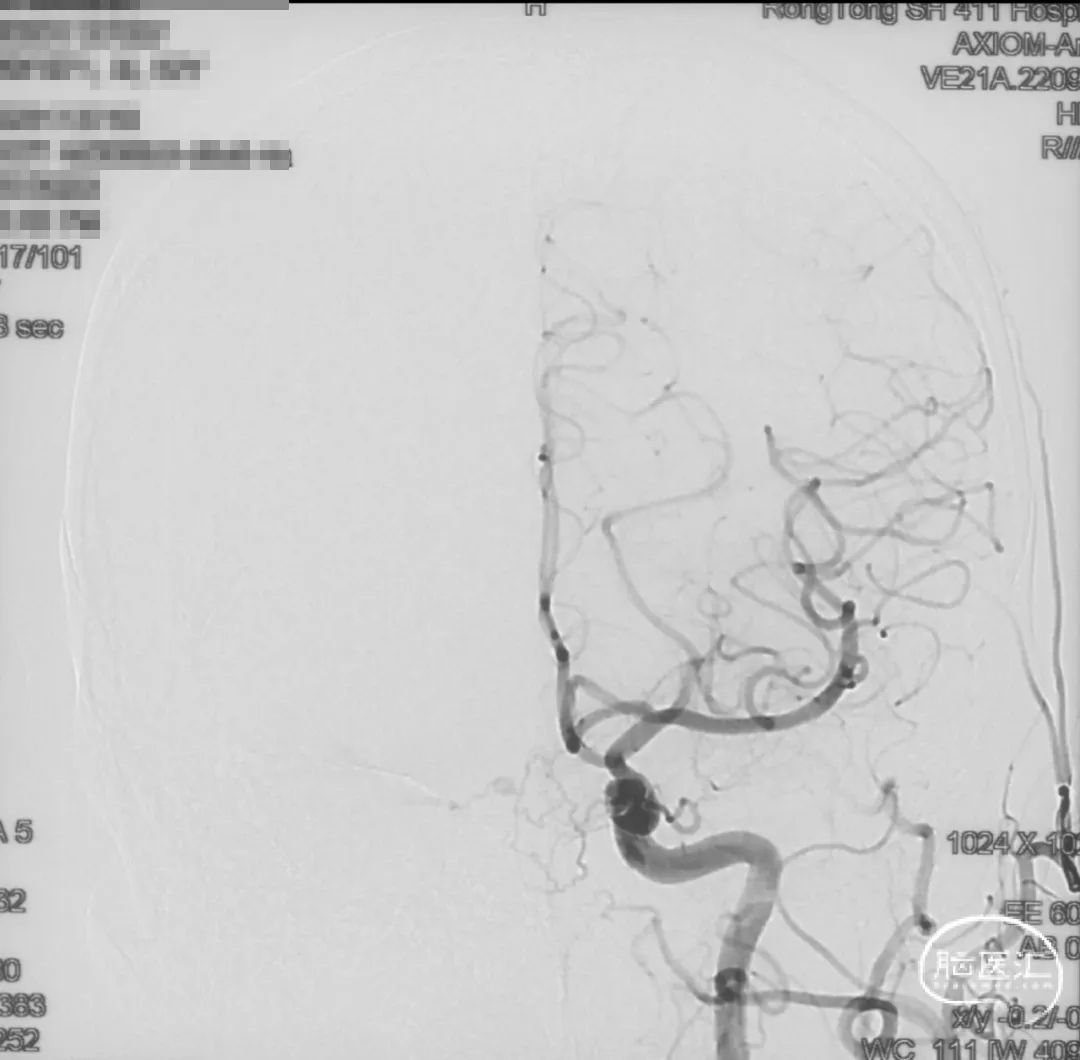

证实为TDAVF,为岩上窦型。R-ECA正侧位见右侧脑膜中动脉分支、枕动脉分支、颞浅动脉分支向瘘口供血,经幕上迂曲扩张的静脉、中脑周围静脉、基底静脉向深部静脉引流。

R-ICA正侧位见右侧脑膜垂体干向瘘口供血

L-ICA正侧位见左侧脑膜垂体干分支向瘘口供血

L-ECA正侧位未见向瘘口供血

L-VA、R-VA正侧位右侧小脑上动脉脑膜支向瘘口供血

结构分析:右侧天幕区硬脑膜动静脉瘘,瘘口位于右侧岩上窦,供血动脉主要包括右侧脑膜中动脉的颞支、岩鳞支,右侧枕动脉分支,右侧颞浅动脉分支,双侧脑膜垂体干,右侧小脑上动脉脑膜支,经幕上迂曲扩张的静脉、中脑周围静脉、基底静脉向深部静脉引流,引流静脉起始部见扩张的静脉球。Cognard分型IV型,Borden分型III型,Lawton分型IV型(岩上窦型)。

选取工作角度,正侧位造影